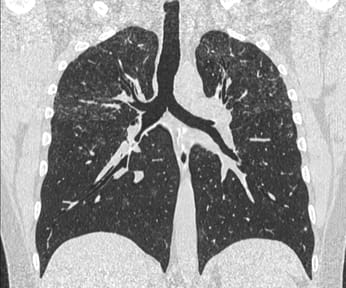

This 55-years old man came with progressive breathlessess, with a history of nonfibrotic hypersensitivity pneumonitis (HP) in 2011 that had progressed to a fibrotic HP in 2016 and then further progressed in 2022.

The video explains the case and the new guidelines and the definition of progressive pulmonary fibrosis (PPF).